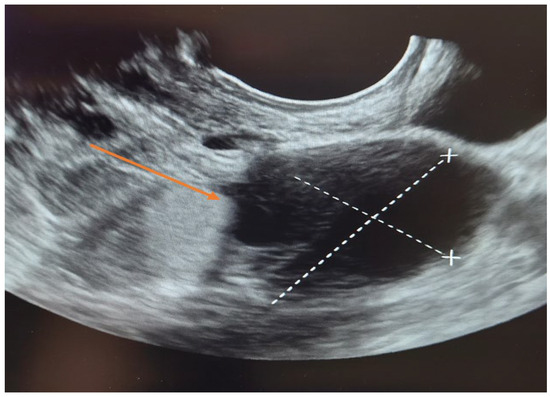

The patient was first evaluated using gynecologic ultrasound, including transvaginal sonography (TVS), which is the first-line diagnostic tool for adnexal masses in clinical practice. Transvaginal sonography (TVS) revealed a complex left adnexal mass with cystic morphology, showing well-defined borders and thin internal septations (Figure 1). Subsequently, magnetic resonance imaging (MRI) was performed as a complementary investigation to provide additional characterization of the lesion and to assist in the differential diagnosis with borderline or malignant ovarian tumors.

Figure 1. Transvaginal sonography (TVS) of the left adnexa ( orange arrow) demonstrating a complex ovarian cyst with cystic morphology, thin internal septations, and well-defined borders.

Transvaginal sonography (TVS) is universally regarded as the first-line imaging modality for the evaluation of adnexal masses and remains central to the preoperative diagnosis of serous cystadenofibromas. Virgilio et al. [51] analyzed a large cohort of histologically confirmed cystadenofibromas and highlighted the characteristic sonographic features—typically unilocular solid or multilocular cystic masses with papillary projections, minimal vascularization on Doppler, and frequent acoustic shadowing—features that help distinguish these lesions from malignant tumors. Alcázar et al. [52] similarly described the wide sonographic spectrum of cystadenofibromas and underscored that TVS, particularly in experienced hands, allows recognition of subtle benign indicators that prevent overtreatment. Thus, TVS is critical in the initial diagnostic approach, both for identifying the mass and for guiding surgical decision-making.

A limitation of this report is the absence of Color Doppler/Power Doppler images and Doppler parameters (PS, PI, RI), which were not recorded at the time of the preoperative examination. Nevertheless, the morphological findings on TVS provided sufficient diagnostic information to guide surgical management.